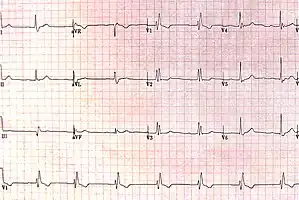

| ECG characteristics of a typical RBBB showing wide QRS complexes with a terminal R wave in lead V1 and a prolonged S wave in lead V6. | |

Diagnosis requires that the QRS complex is greater than 120 ms and an rsR' wave is present in lead V1 or V2.[2] The T waves are generally flipped in V1 and V2.[2] When the QRS duration is less than 120 ms, but the other criteria are present, it is called an incomplete RBBB.[1] Its presence does not interfere with the diagnosis of a heart attack.[1]

The criteria to diagnose a right bundle branch block on the electrocardiogram:

- The heart rhythm must originate above the ventricles (i.e., sinoatrial node, atria or atrioventricular node) to activate the conduction system at the correct point.

- The QRS duration must be more than 100 ms (incomplete block) or more than 120 ms (complete block).[4]

- There should be a terminal R wave in lead V1 (often called "R prime," and denoted by R, rR', rsR', rSR', or qR).

- There must be a prolonged S wave in leads I and V6 (sometimes referred to as a "slurred" S wave).

The T wave should be deflected opposite the terminal deflection of the QRS complex. This is known as appropriate T wave discordance with bundle branch block. A concordant T wave may suggest ischemia or myocardial infarction.